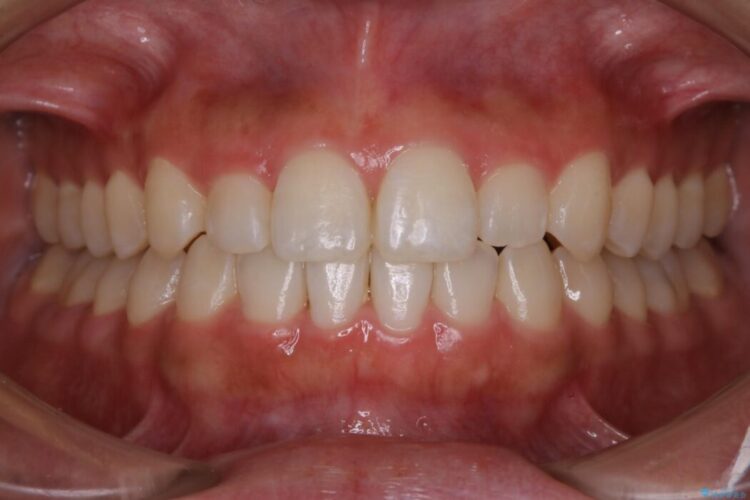

治療後について

反対咬合の歯も整ったアーチに収まり、きれいに仕上がりました。

今回のケースでは前歯部の軽い凹凸のみであったため部分矯正の適応範囲に該当していました。

適応例は限られますが、部分矯正は全体矯正と比べると矯正期間が短く、費用も安く済みます。